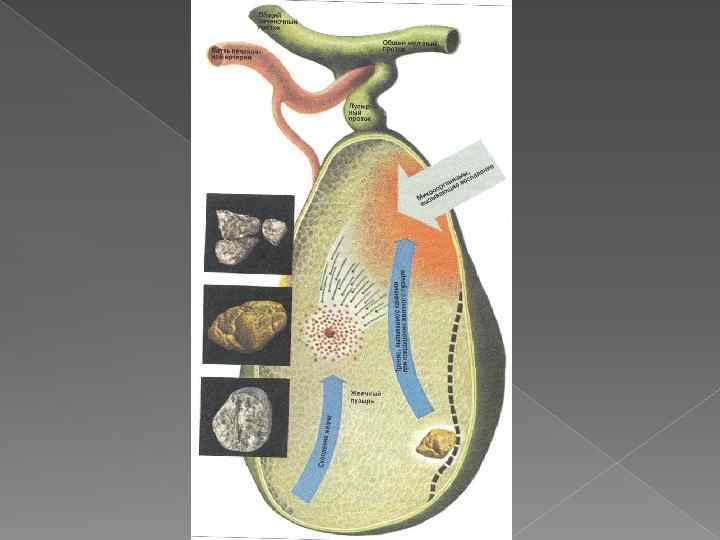

Желчные камни ЯВЛЯЮТСЯ КОНКРЕМЕНТАМИ, ОБРАЗУЮЩИМИСЯ В ЖЕЛЧИ В РЕЗУЛЬТАТЕ КРИСТАЛИЗАЦИИ. ХОЛЕЛИТИАЗ – ОБРАЗОВАНИЕ ЖЕЛЧНЫХ КАМНЕЙ Желчные камни построены главным образом из органических веществ, компонентов желчи. Чаще всего желчные камни построены из трех компонентов желчи: холестерина, билирубина и кальция.

Желчные камни ЯВЛЯЮТСЯ КОНКРЕМЕНТАМИ, ОБРАЗУЮЩИМИСЯ В ЖЕЛЧИ В РЕЗУЛЬТАТЕ КРИСТАЛИЗАЦИИ. ХОЛЕЛИТИАЗ – ОБРАЗОВАНИЕ ЖЕЛЧНЫХ КАМНЕЙ Желчные камни построены главным образом из органических веществ, компонентов желчи. Чаще всего желчные камни построены из трех компонентов желчи: холестерина, билирубина и кальция.

Острый холецистит, возникающий на почве желчнокаменной болезни, составляет 85 -90%. В результате закупорки камнем протока желчного пузыря прекращается поступление желчи в кишечник, повышается давление её на стенки пузыря. Стенки растягиваются, в них ухудшается кровоток, что способствует развитию воспаления.

Острый холецистит, возникающий на почве желчнокаменной болезни, составляет 85 -90%. В результате закупорки камнем протока желчного пузыря прекращается поступление желчи в кишечник, повышается давление её на стенки пузыря. Стенки растягиваются, в них ухудшается кровоток, что способствует развитию воспаления.